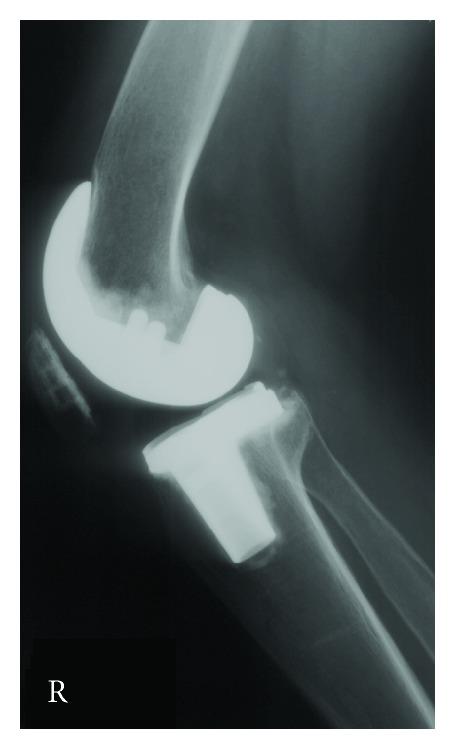

The definitive treatment for advanced joint destruction in the late stages of rheumatoid arthritis can be successfully treated with total joint arthroplasty. Total knee arthroplasty has been shown to be a well-proven modality that can provide pain relief and restoration of mobility for those with debilitating knee arthritis. It is important for rheumatologists and orthopedic surgeons alike to share an understanding of the special considerations that must be addressed in this unique population of patients to ensure success in the immediate perioperative and postoperative periods including specific modalities to maximize success.

类风湿关节炎晚期严重关节破坏的最终治疗方法是全关节置换术,该方法已被证明是一种行之有效的治疗方式,能为患有严重膝关节炎的患者缓解疼痛并恢复活动能力。对于风湿病学家和骨科医生而言,共同理解在这类特殊患者群体中必须考虑的特殊因素非常重要,以确保在围手术期和术后短期内获得成功,这包括采用特定方式来实现最大程度的成功。